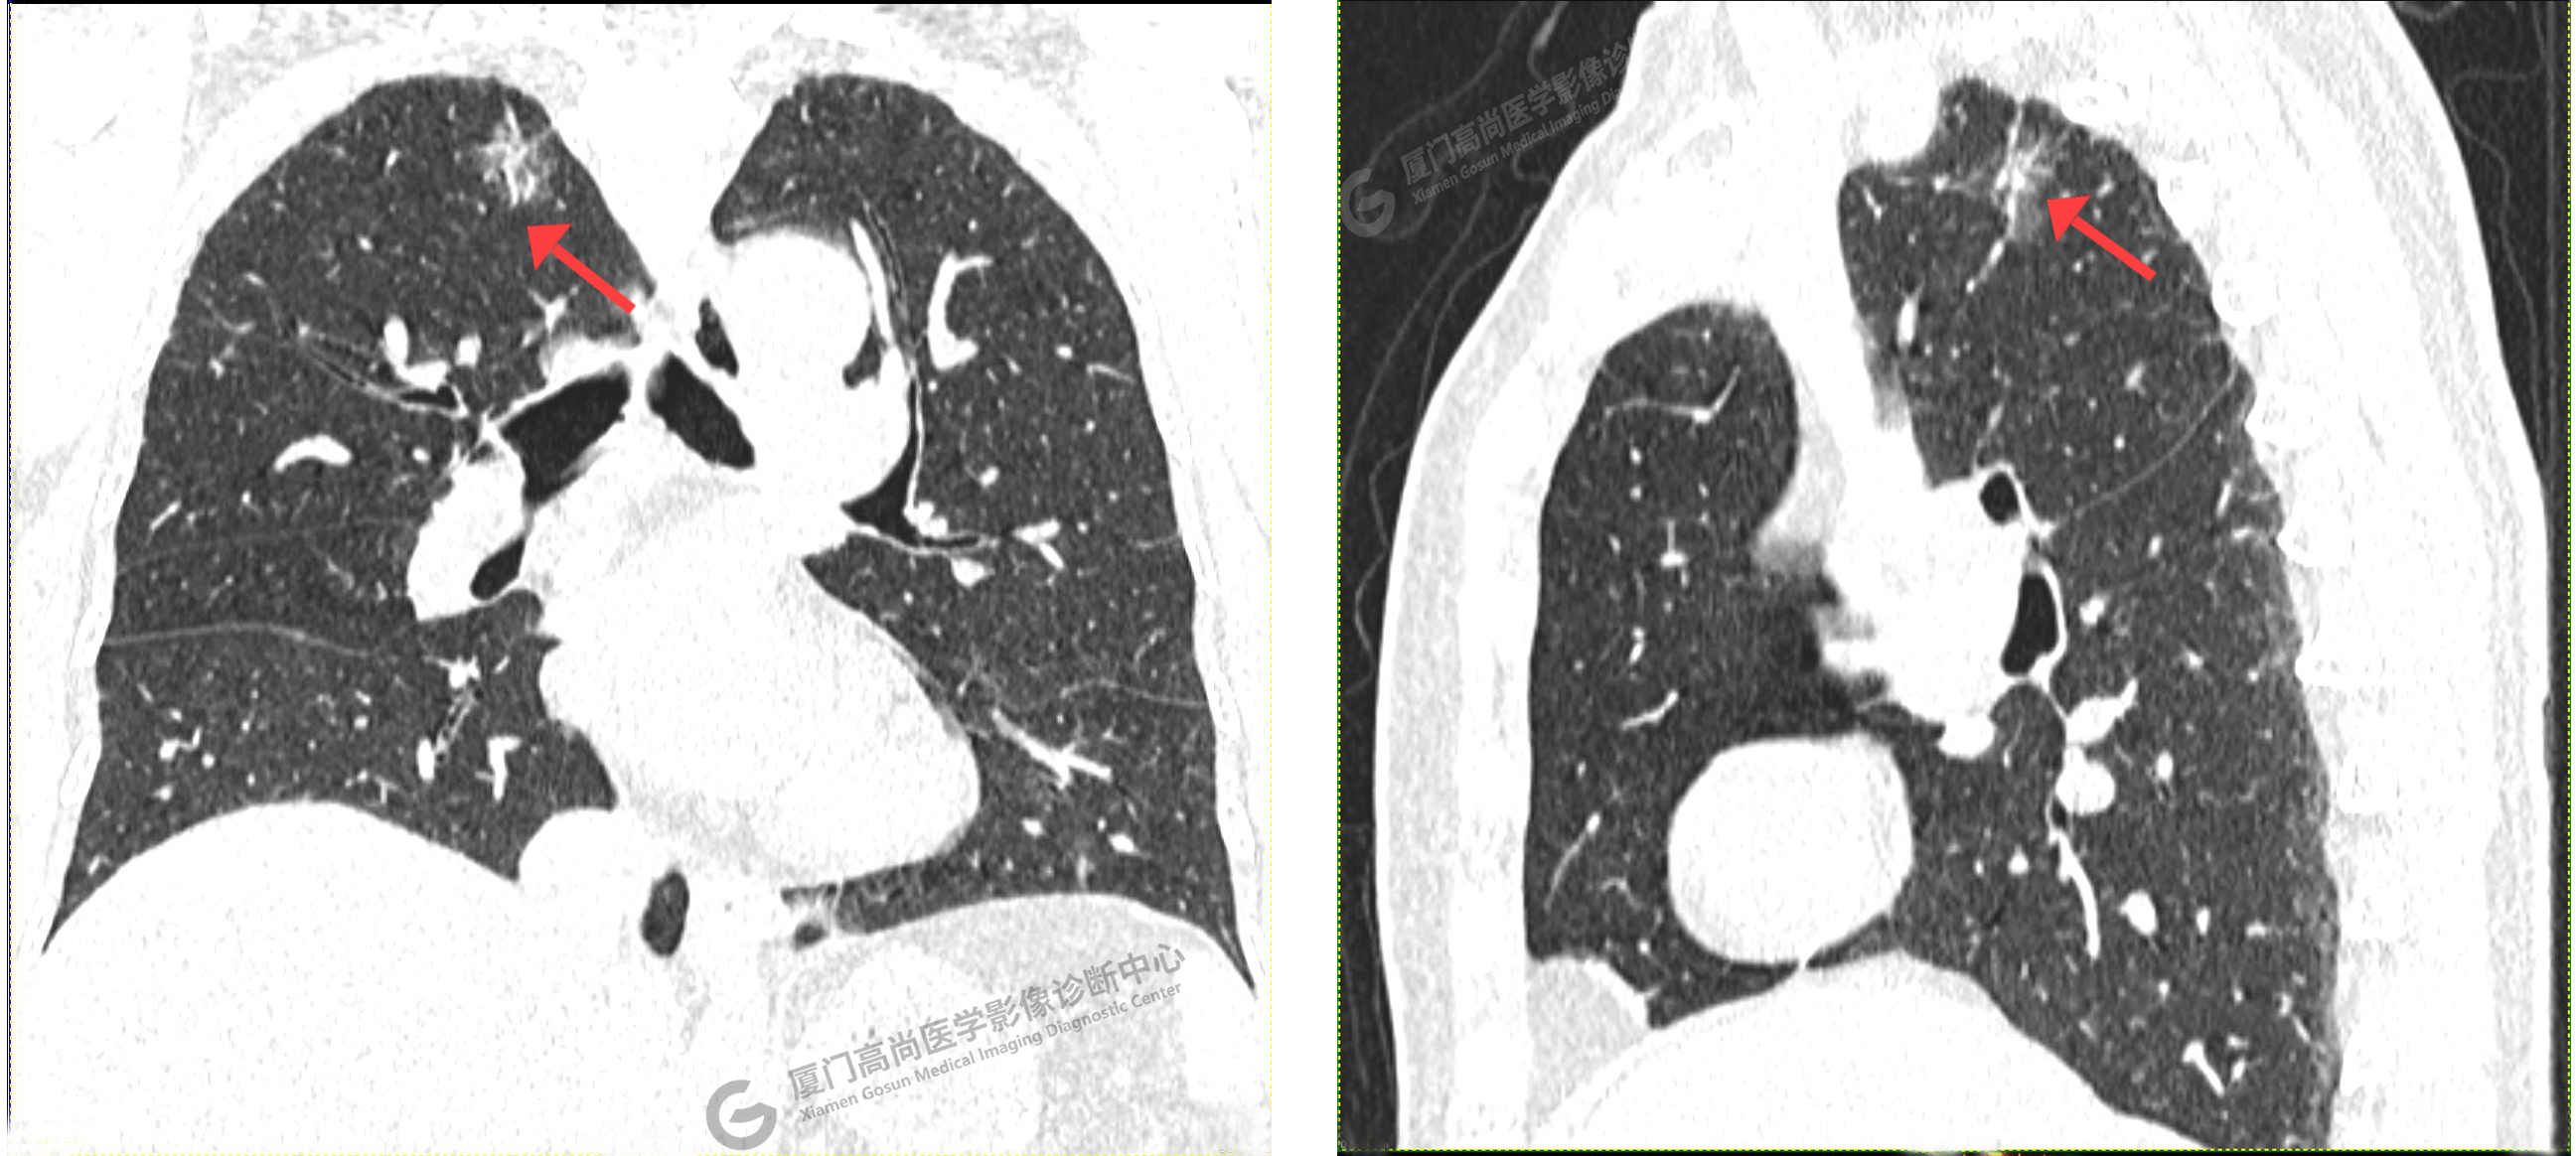

CT影像圖

CT示:左肺上葉團(tuán)片狀磨玻璃密度影,腫瘤性病變(IAC?)可能,建議PET/CT檢查。